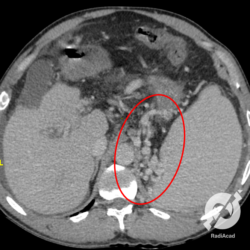

Aqui outro paciente com hepatopatia crônica, que tem um fígado lobulado, com atrofia do lobo direito e uma proeminência do lobo esquerdo. Todo o fígado é heterogêneo, com imagens nodulares difusas de tamanhos variados, que correspondem predominantemente a nódulos de regeneração. Também observamos uma pequena quantidade de líquido livre subfrênico direito envolvendo parcialmente o fígado (círculo). Interessante notar que embora seja mais comum pacientes hepatopatas apresentarem distúrbios de coagulação manifestados por sangramentos, eventualmente o distúrbio de coagulação se manifesta como fenômenos trombóticos e neste caso como um infarto esplênico (seta vermelha).